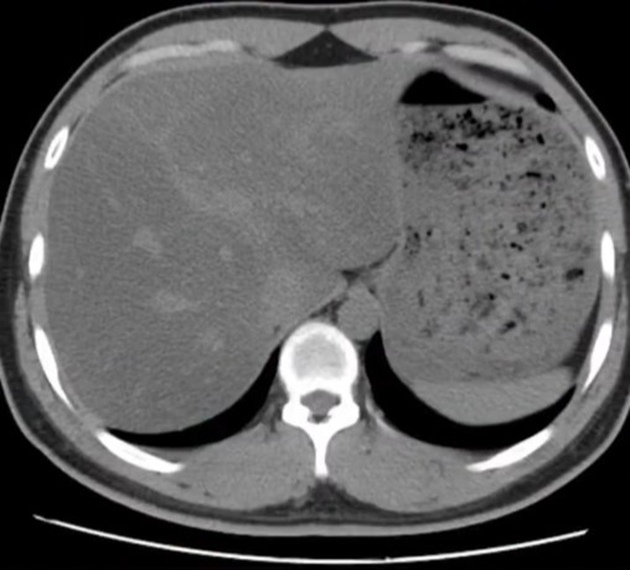

Tình trạng gan nhiễm mỡ của nữ kế toán trở nặng sau khi giảm 10kg (Ảnh BV cung cấp)

Sau vài tháng, cô giảm được 10kg, vòng eo nhỏ lại rõ rệt. Tuy nhiên, kết quả tái khám sau 6 tháng ăn như vậy lại khiến cô ngỡ ngàng. Dù chỉ nặng 47kg nhưng tình trạng gan nhiễm mỡ nhẹ không những không giảm đi mà tăng lên 2 cấp độ, đạt tới mức nặng kèm suy giảm chức năng thải độc gan và có sỏi thận nhỏ. Cô cũng bị suy giảm miễn dịch, rối loạn nội tiết (rụng tóc, chậm kinh) do ché độ ăn này.